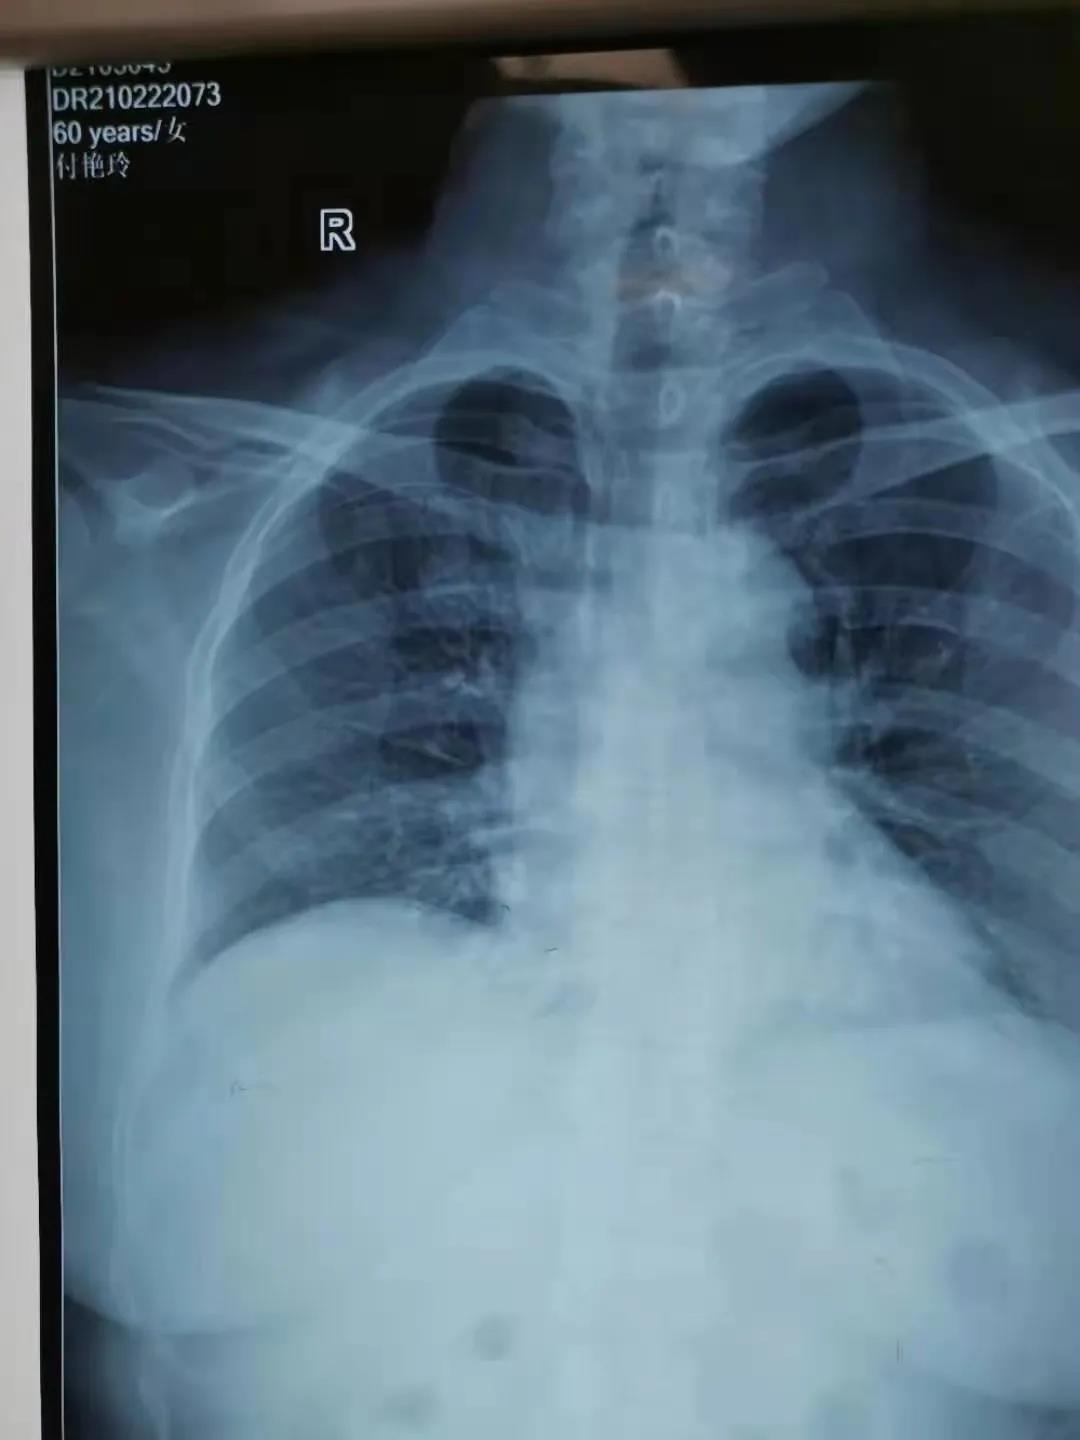

2月22日,由郸城县第二医疗健康服务集团郸城县中医院肿瘤血液科护士长刘晓娟,护士丁星文、马慧、张玉霞成立的静脉治疗专科小组,在经过了数例PICC置管中进行心电腔内(ECG)定位与x线下定位结果的比较后成功运用了ECG定位技术置管,此项技术的成功开展,标志着医院PICC置管定位技术又上新台阶!

有研究表明中心静脉尖端位置过浅,会增加静脉血栓形成的风险,缩短导管留置时间,位置过深则会进入右心房、右心室或下腔静脉可能会导致心律失常、心腔病变、三尖瓣功能障碍或病变、血栓形成,因此对PICC尖端进行定位显得尤为重要。

ECG定位技术通过一“进”两“退”的方式(一进:当导管尖端到达CAJ时,可见高尖P波,进入右心房后P波双向,由高尖再转低;一退:当导管尖端从右心房退回上腔静脉时P波恢复正常。再退:导管继续后退2-3 cm到达最终正确的位置。)判断导管尖端位置,及时纠正导管异位、极大的提高了导管尖端位置定位的准确性,避免了因反复调整导管位置所致的并发症(静脉炎、导管相关感染、血栓等)及因导管异位而重复拍片,保证了患者安全,提高了工作效率。③7